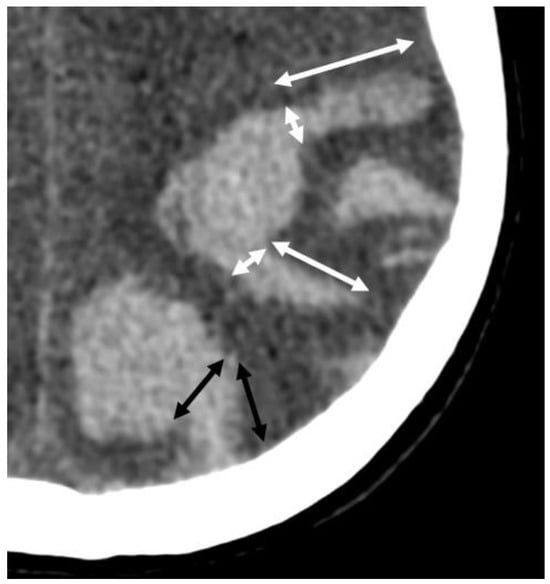

6.6. Cortical Calcifications

- Rodrigues, M.A.; Samarasekera, N.; Lerpiniere, C.; Humphreys, C.; McCarron, M.O.; White, P.M.; Nicoll, J.A.R.; Sudlow, C.L.M.; Cordonnier, C.; Wardlaw, J.M.; et al. The Edinburgh CT and genetic diagnostic criteria for lobar intracerebral haemorrhage associated with cerebral amyloid angiopathy: Model development and diagnostic test accuracy study. Lancet Neurol. 2018, 17, 232–240. [Google Scholar] [CrossRef]

- Rasing, I.; Voigt, S.; Koemans, E.A.; van Zwet, E.; de Kruijff, P.C.; van Harten, T.W.; van Etten, E.S.; van Rooden, S.; van der Weerd, L.; van Buchem, M.A.; et al. Occipital Cortical Calcifications in Cerebral Amyloid Angiopathy. Stroke 2021, 52, 1851–1855. [Google Scholar] [CrossRef]